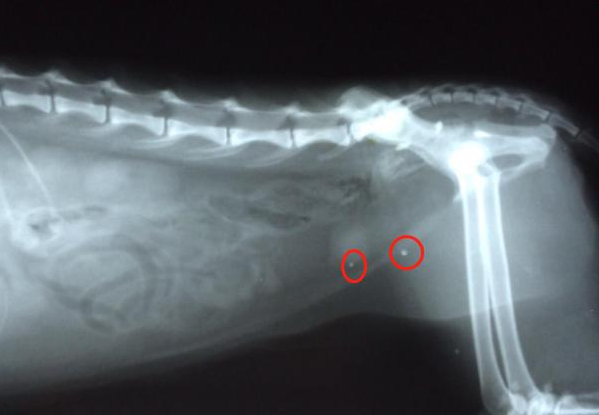

猫咪的泌尿系统疾病是让所有铲屎官都觉得头疼的一类疾病 , 而其中的膀胱结石是它们的常见病 , 发病率非常高 , 而且猫咪会极度痛苦 , 还会造成肾衰竭等严重的病症 , 题主 说到的多喝水对这类疾病是有着一定的帮助的 。

尿液PH值:当尿液的PH值过低或者过高时 , 都会形成尿液结晶 , 当尿液中的结晶越来越多 , 浓度很高的时候 , 就会变成结石 , 堵塞尿道 。

尿量:其实在猫咪身体健康的时候 , 也会尿液中也会出现结晶 , 但是但饮水量充足 , 这些小结晶就会随着尿液排出 , 但尿量过少 , 结晶就会在膀胱中沉淀 , 形成结石 。

膀胱结石会造成膀胱堵塞 , 而在出现堵塞后的24小时左右就会造成肾衰竭的情况 , 接下来会引发一系列的连锁反应 , 各个器官都会出现相应的问题 , 最后甚至造成死亡!